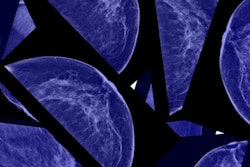

To do this, the researchers culled 250 cases categorized as BI-RADS 4 or 5 from four University of California medical centers. Ten academic breast imaging radiologists reviewed the cases, assigning each a BI-RADS category, estimating the percent likelihood of DCIS or invasive cancer, and designating a confidence rating based on a scale of 1 to 5 (1 = low, 5 = high) after reviewing screening and diagnostic mammograms as well as ultrasound images. The researchers then generated receiver operating characteristic (ROC) curves based on likelihood estimates for the presence of invasive cancer and DCIS assigned by each reader.

Of the 250 test cases, 62% were benign and 38% were malignant. There were 26 cases of DCIS (10%), 20 invasive cancers (8%), and 48 cases of invasive cancer with DCIS (19%).

The group found that the area under the curve (AUC) values for the 10 radiologists ranged from 0.83 to 0.91 for predicting the presence of invasive cancer (an AUC of 1 indicates perfect accuracy). AUC values for predicting the presence of DCIS were lower, ranging from 0.73 to 0.83, while values for predicting DCIS as a concomitant finding with invasive cancer were lower still, ranging from 0.58 to 0.78.